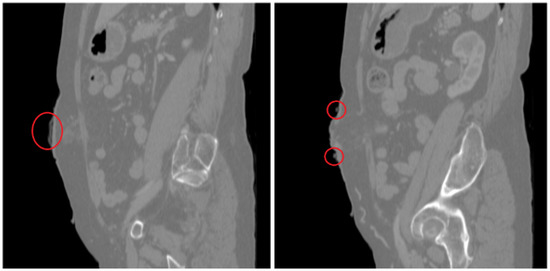

2.3.4. CT Scans

2.3.5. Processing of CT Scans and Design of the Ostomy Patch